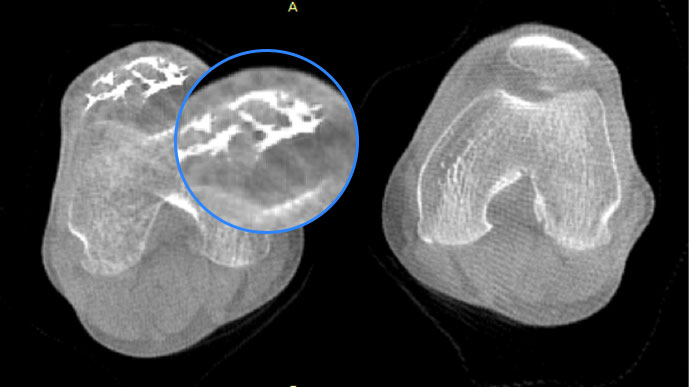

· 补位CT,提供负重位三维影像

· 引领普放走向三维精准诊断时代

膝关节

精准诊断

手术方案规划